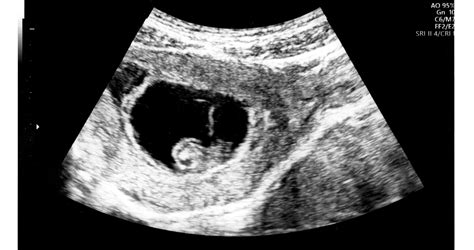

A kombinált teszt egy kockázatbecslő szűrővizsgálat, amely ultrahangvizsgálatból és vérvételből áll. Az ultrahang során a magzat bizonyos anatómiai jellegzetességeit vizsgálják, úgynevezett ultrahangos markereket, mint például a tarkóredő vastagsága (NT), az orrcsont megléte vagy hiánya, valamint az áramlási viszonyok (ductus venosus, tricuspidális regurgitáció). A vérvétel során pedig két, a méhlepény által termelt magzati plazmafehérje, a PAPP-A (terhességgel összefüggő plazmafehérje) és a free ß-hCG (human chorionic-gonadotropin szabad ß-egysége) koncentrációját mérik. Ezeket az értékeket az anyai életkorral és egyéb tényezőkkel együtt értékelik ki, hogy megállapítsák a rendellenességek kialakulásának kockázatát.

A kombinált teszt a terhesség 11. és a betöltött 14. hete között végezhető el, optimális ideje a betöltött 12-13. hét. A vizsgálat pontos elvégzéséhez elengedhetetlen a Fetal Medicine Foundation (FMF) kritériumainak való megfelelés, és hogy a vizsgálatot FMF licenccel rendelkező szakember végezze. Az FMF (Fetal Medicine Foundation) egy nemzetközi szervezet, amely a magzati orvoslás területén végez kutatásokat és képzéseket, valamint kidolgozza a magzati vizsgálatokra vonatkozó nemzetközi protokollokat.

A vizsgálat során az anyai életkorból számolt kiinduló kockázatot módosítják az ultrahang és a vérvizsgálat során mért markerekkel. Ezek az értékek külön-külön emelhetik vagy csökkenthetik a kockázatot. Fontos megjegyezni, hogy az egyes paraméterek tized milliméter pontossággal mérendőek, és pár tized milliméteres tévedés is fals eredményt adhat.